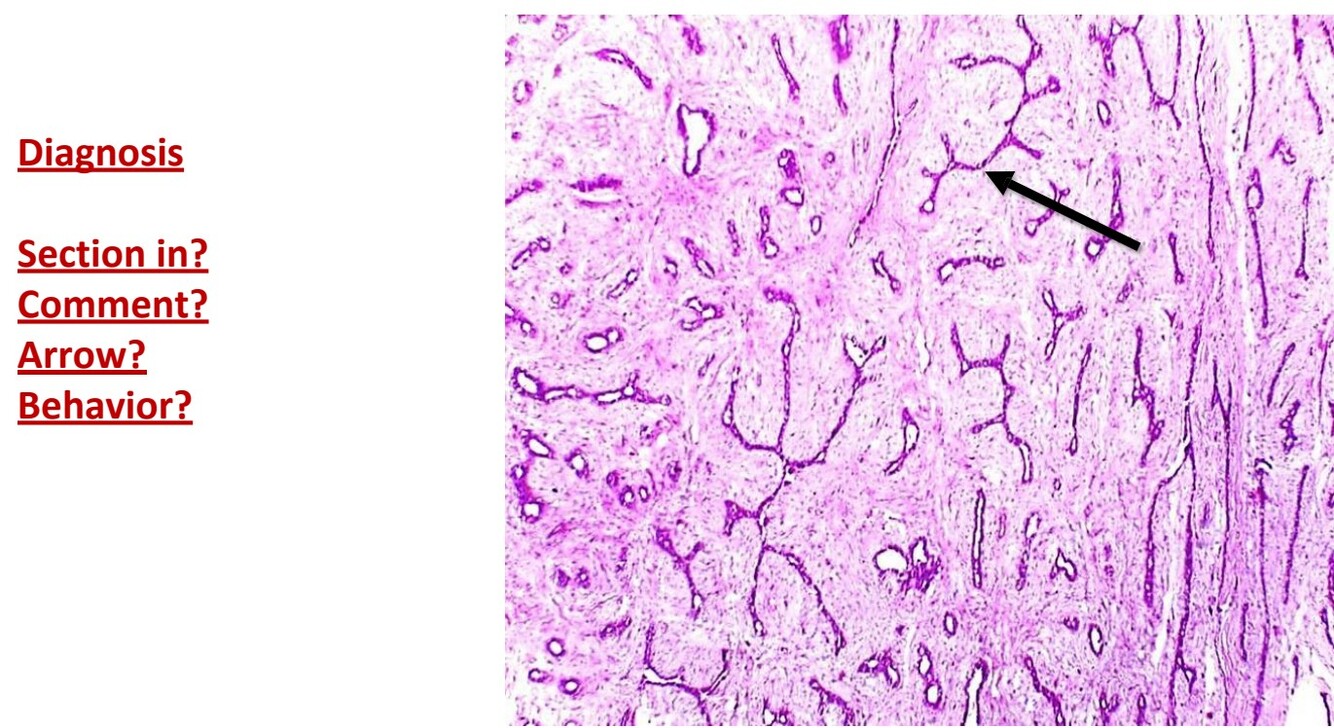

Peri-canalicular fibroadenoma

Section in capsulated benign tumor

Proliferated ducts with oval cut in section with patent lumen

Delicate fibrous tissue

Arrow points to duct (non invasive)